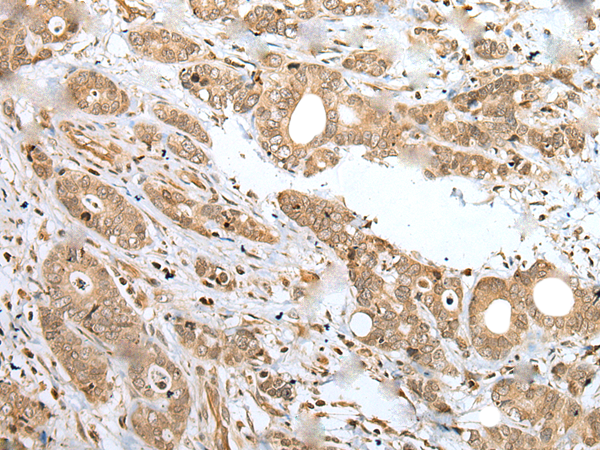

IHC positive control: |

Human gastric cancer |